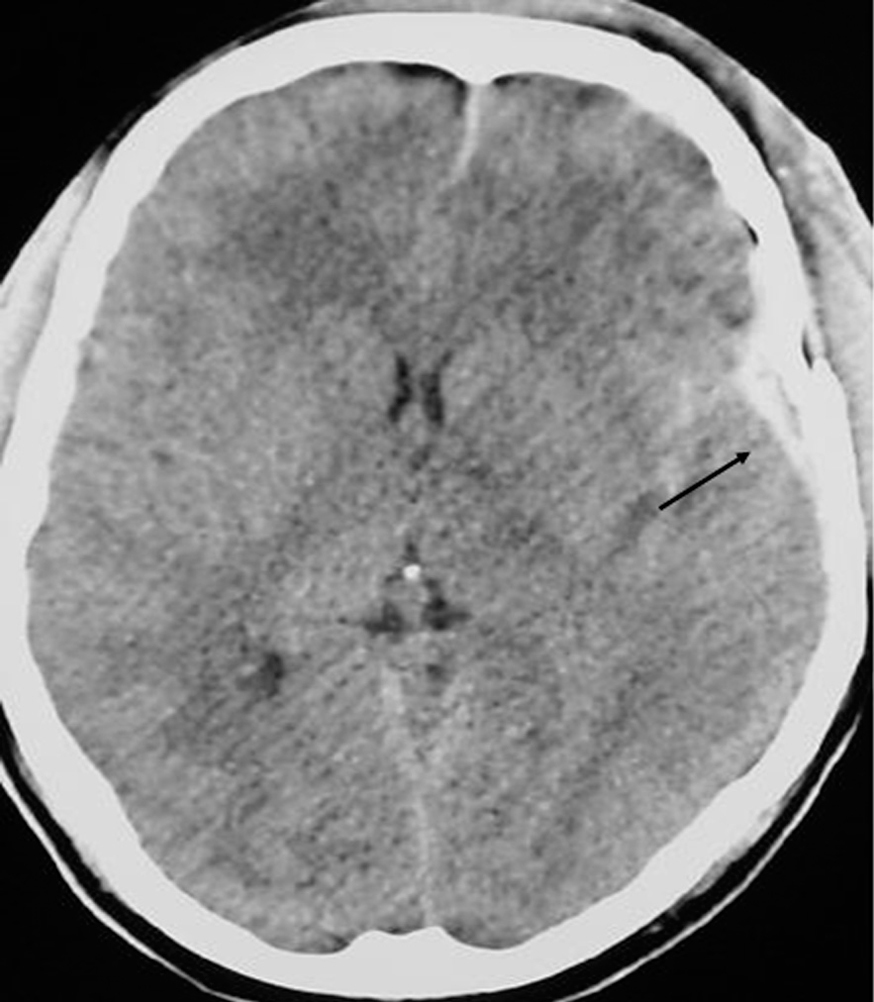

Presentamos el caso de un hombre de 24 años, que sufrió un traumatismo craneoencefálico (TCE), ingresando en una Unidad de Cuidados Intensivos (UCI) con un Glasgow Coma Score de 7 puntos. La tomografía axial computarizada (TAC) craneal mostró un hematoma extraaxial temporal izquierdo no subsidiario de cirugía (fig. 1). A continuación se realizó un dúplex transcraneal con codificación de color (DTCC) que confirmó la presencia de dicho hematoma, mostrando un tamaño de 45 x 9 mm (fig. 2). El hematoma extraaxial se pudo seguir en las siguientes 96 horas mediante DTCC a pie de cama sin apreciarse cambios en su tamaño. Se realizó entonces nueva TAC craneal que corroboró los hallazgos del DTCC. Posteriormente se pudo retirar sedación y extubar, encontrándose el paciente al alta consciente y sin focalidad neurológica.

Figura 1.